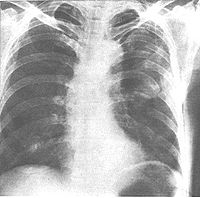

肋骨骨折的诊断主要依据受伤史、临床表现和X线胸片检查。按压胸骨或肋骨的非骨折部位(胸廓挤压试验)而出现骨折处疼痛(间接压痛),或直接按压肋骨骨折处出现直接压痛阳性或可同时听到骨擦音、手感觉到骨摩擦感和肋骨异常动度,很有诊断价值。X线胸片上大都能够显示肋骨骨折,但是,对于肋软骨骨折、“柳枝骨折”、骨折无错位、或肋骨中段骨折在胸片上因两侧的肋骨相互重叠处,均不易发现,应结合临床表现来判断以免漏诊。无合并损伤的肋骨骨折称为单纯性肋骨骨折。除了合并胸膜和肺损伤及其所引起的血胸或(和)气胸之外,还常合并其他胸部损伤或胸部以外部位的损伤,诊断中尤应注意。第1或第2肋骨骨折常合并锁骨肩胛骨骨折,并可能合并胸内脏器及大血管损伤、支气管气管断裂、或心脏挫伤,还常合并颅脑伤;下胸部肋骨骨折可能合并腹内脏器损伤,特别是肝、脾和肾破裂,还应注意合并脊柱骨盆骨折。但是,当第7肋以下的肋骨骨折时,由于骨折处肋间神经受刺激,产生传导性腹痛,应注意与腹腔脏器损伤所引起的示位性腹痛相鉴别。

肋骨骨折形态多为横断形,亦有斜行,可单发或多发。大多为一侧性。第1与第2肋骨位在锁骨之后,第11与12肋骨为游离短肋,发生骨折机会较少。